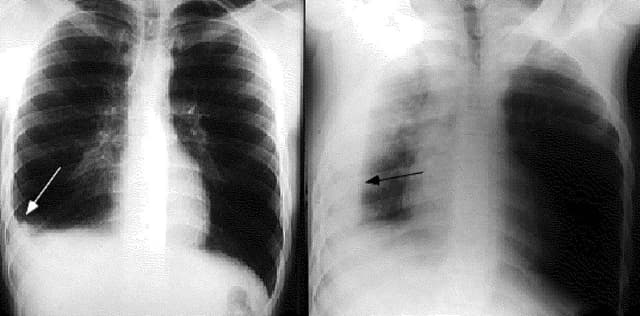

tràn dịch màng phổi

Triệu chứng tràn dịch màng phổi cần quan tâm

Đau ngực là triệu chứng tràn dịch màng phổi thường gặp. Triệu chứng này kéo dài sẽ gây ảnh hưởng xấu tới sức khỏe. Tràn dịch màng phổi nếu không được xử trí kịp thời sẽ gây biến chứng nguy hiểm. Theo các chuyên gia y tế, tràn dịch màng phổi là biểu hiện hoặc biến […]